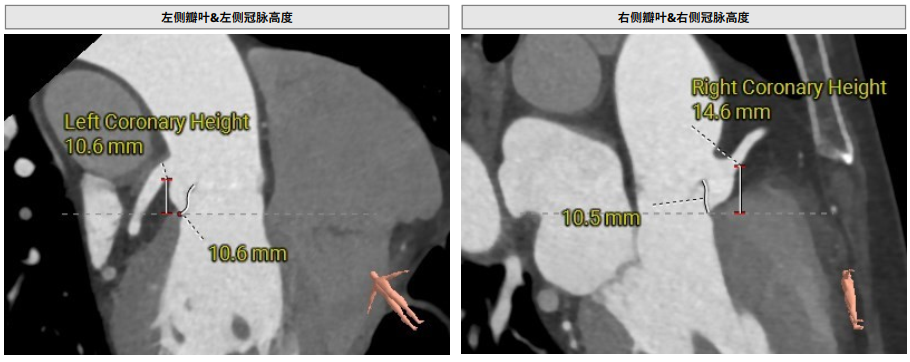

术前影像评估提示,患者为典型三叶瓣结构,瓣窦对称分布,无明显钙化沉积,主动脉瓣环直径23.9mm,左心室流出道直径25.1mm,双侧冠脉开口高度充足(左冠10.6 mm,右冠14.6mm),升主动脉直径为34.3mm。瓣膜周围结构解剖条件良好,左室与主动脉夹角为138°。

CTA评估(上下滑动查看更多照片)